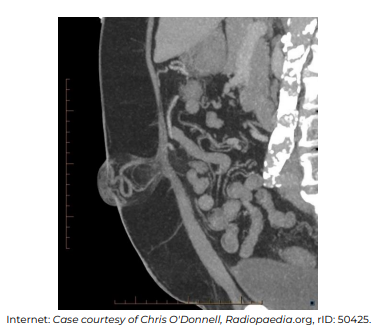

No que diz respeito à interpretação e ao diagnóstico nosológico que explica os achados na imagem apresentada, assinale a alternativa incorreta.